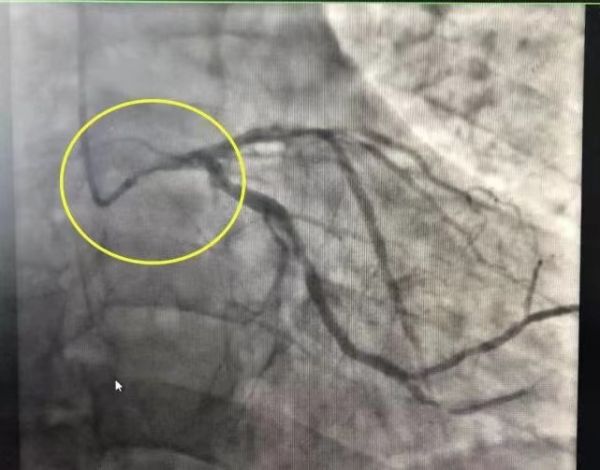

FDA表示,召回这款心脏泵的原因是,其泵导管在手术过程中可能会刺穿心脏左心室壁,并导致严重不良后果。包括左心室穿孔、离壁破裂、高血压供血不足以及死亡。数据显示,该产品已导致129人重伤,其中49人死亡,66000多件产品存在安全隐患。

Impella心脏泵主要用于心衰患者,特别是在冠心病患者做冠脉支架时可以起到“保护”作用。另一类是用于晚期心衰、急性心梗或爆发性心肌炎导致心源性休克后,需要临时性地辅助心脏泵血功能,以维持血流稳定、保护心肌,属于过渡性措施。具体而言,就是Impella心脏泵可以通过股动脉穿刺进到心脏内,通过里面很小的一个泵将血液抽出来,再打到主动脉里去,有效减轻心脏的负担。

3月底Abiomed公司召回其6个型号的Impella心脏泵,这次是历史上最大规模的召回。主要措施是更换使用说明书、新增关于心室穿孔风险的5条警告而已。据业内人士称,Impella设备相对常见的不良反应是容易在心室内贴壁,造成引流不畅,而穿破心脏等并发症相对少见,召回所做的是进行技术修正与改良,而非否定这类器械的临床应用价值。所以应该是这款产品某个批次的问题,而不是整体设计上的问题。